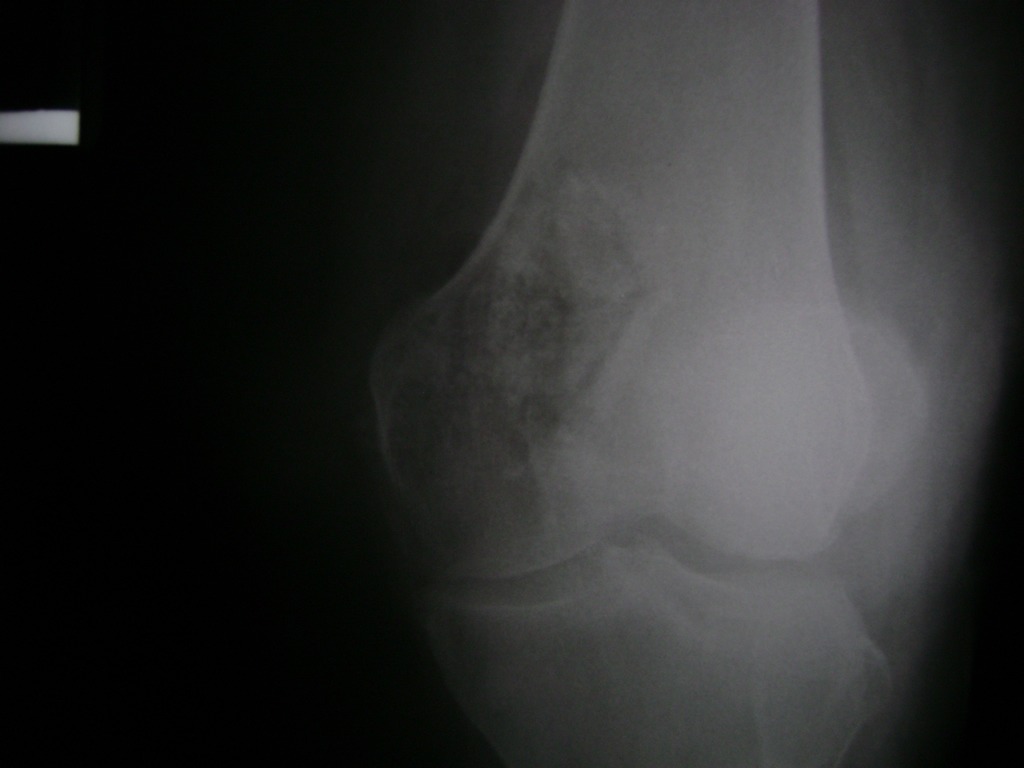

La artroscopia de rodilla es un cirugía en el cual la estructura interna de la articulación es examinada ya sea para realizar un diagnostico o para realizar un tratamiento, este procedimiento se realiza utilizando un instrumento parecido a un pequeño tubo llamado artroscopio.

La artroscopia se popularizo en 1960 y hoy en día es muy común en todo el mundo. Típicamente, es realizada por cirujanos ortopédicos de manera ambulatoria. Cuando se realiza de manera ambulatoria los pacientes pueden regresar a casa después de la operación, no se requiere quedarse en hospital.